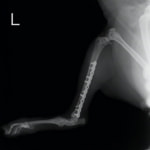

トイプードル 右遠位橈尺骨短斜骨折のALPSによる内固定

Locking Compression Plate

LCPは、スクリュー(ネジ)とプレート(金属の板)をロックする特殊な構造により骨折部位を固定する新しい世代のプレートシステムです。ひとつのホールでロッキングスクリューとスタンダードスクリューの使用を選択できるユニークな構造をしているため、骨折断端間の圧迫を目的とした従来型プレート固定法に加え、高い角度安定性を有するロッキングスクリューを用いた固定法の選択が可能です。従来のプレートシステムでは困難だった部分の骨折や癒合不全の症例に高い治療効果をもたらします。